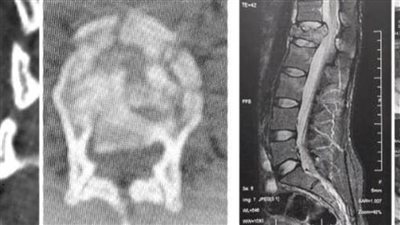

جراحة عاجلة لتثبيت الفقرات الصدرية والقطنية وتوسيع القناة العصبية